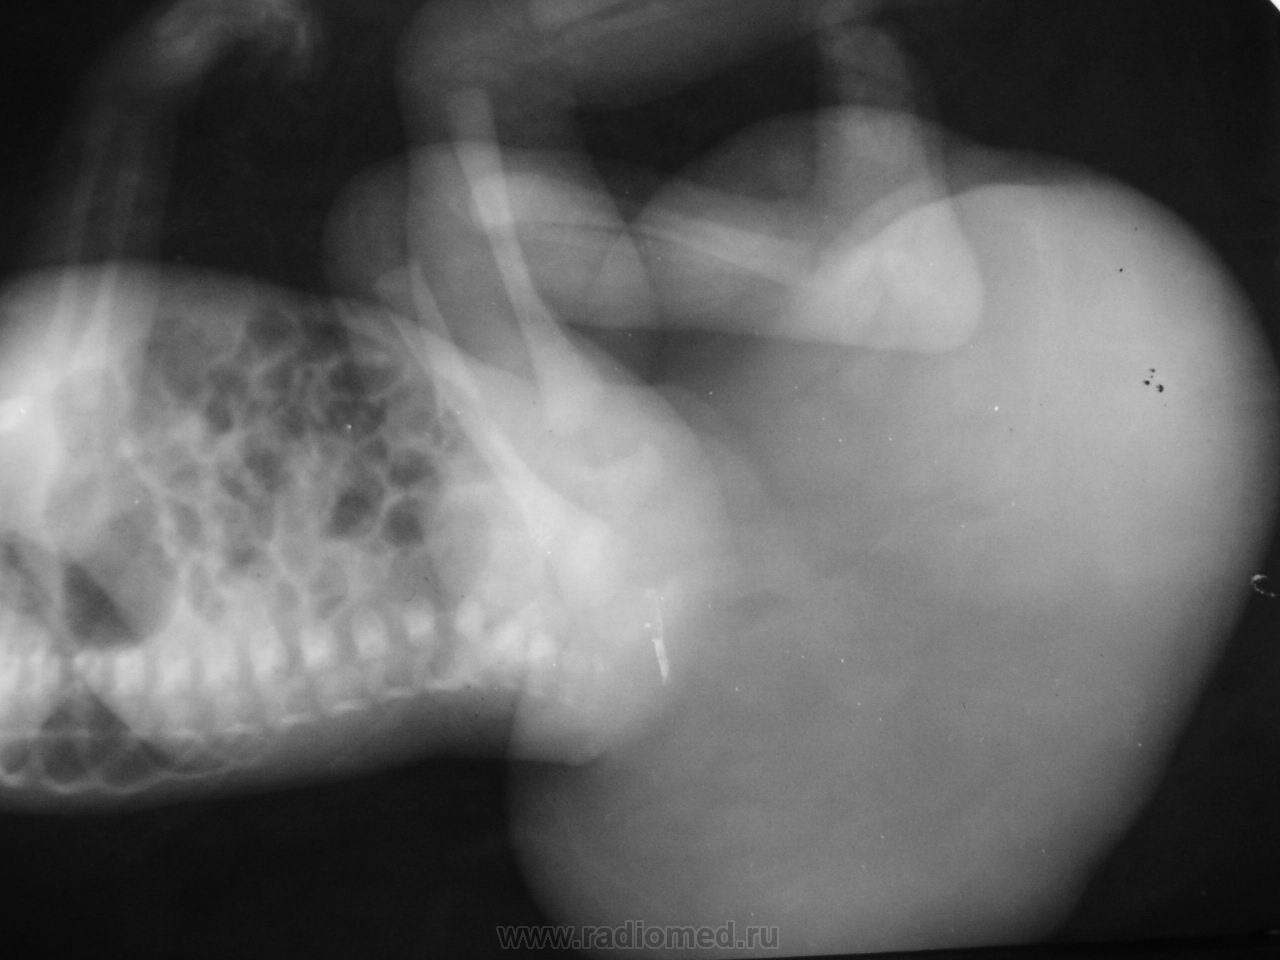

Не сразу поймешь что это... огромная, больше головы опухоль из области кресца. Ваше мнение?

Мягкотканное - тератома?

Похожа на крестцово-копчиковую тератому.

Или огромное менигоцеле.

Основной признак, по которым различают такие тератомы и врожденные аномалии с менингоцеле - это поведение кресцовых позвонков. При тератоме они целые, при пороке развития позвоночника и оболочек - изменены. А здесь нет последнего кресцового позвонка. Второй признак - менингоцеле - однородной структуры, без включений. Это и сыграло главную роль - в нашем случае, хоть костных образований внутри и не было, структура - неоднородная.

Ребенка оперировали, подтвердился диагноз тератомы, но операцию он не перенес...